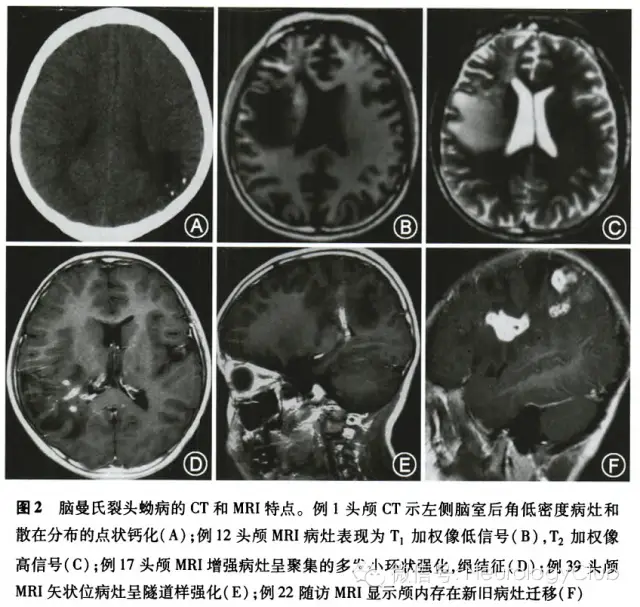

在长期随访(随访时间点为4个月、6个月、12个月、34个月和96个月)中均无患者失访,未行手术治疗仅口服吡喹酮治疗的患者18例预后良好,治疗前影像学检查T2WI呈长T2信号,中间混杂信号(图1A),增强后呈串珠状强化(图1B),大剂量吡喹酮给药后复查影像学T2WI病灶基本消退(图1C),强化病灶消失(图1D),消失时间分别为治疗后4个月(3例)、6个月(9例)、12个月(3例)、16个月(1例)、34个月(2例)。在随访期间,1例原左顶叶病变开颅手术患者未取到活虫,于术后6个月影像学复查示右侧小脑半球出现新的病灶。38例患者基本达到临床痊愈,4例残留不同程度的肢体瘫痪。9例患者存在不同程度癫痫发作,需长期服用抗癫痫药物,其中1例经吡喹酮治疗痊愈患者在96个月时再发抽搐,影像学随访为双顶叶软化萎缩。

所有患者均接受至少2次MRI扫描(在诊断时和治疗后)。42例患者中单侧强化孤立病灶者41例,占97.6%(41/42),双侧强化病灶者l例,占2.4%(1/42)。幕上病灶40例,占95.2%(40/42),幕下病灶2例,占4.8%(2/42)。病灶主要以额顶叶为主,占69.0%(29/42)。头颅MRI病灶表现为T1加权像低信号(图2B),T2加权像高信号,部分患者可见点状的混杂信号(图2C)。增强MRI显示38例患者病灶呈聚集的多发小环状强化,典型者表现为绳结状(图2D);14例患者病灶呈隧道样强化,特别在矢状位和冠状位明显(图2E),隧道一般长l-5cm,宽0.3-1.2cm,T1加权像为低信号、稍高信号或等信号,T2加权像为高信号。此外,随访MRI发现13例患者存在新旧病灶迁移(图2F),从额顶到顶枕5例;从额顶到颞叶3例;从顶叶到小脑半球2例;从左额叶到右额叶再到枕叶l例;从脑干到丘脑到顶叶1例;从基底节到额顶到胼胝体1例。